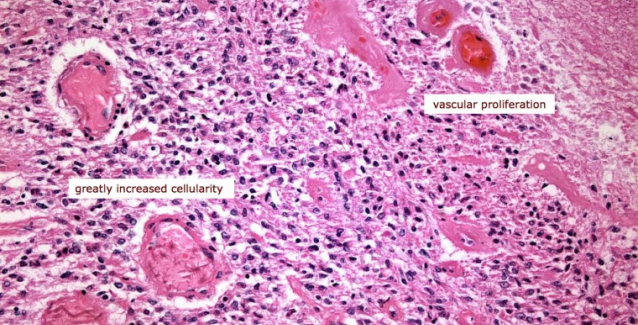

Микрофотографии гистологии глиобластомы головного мозга